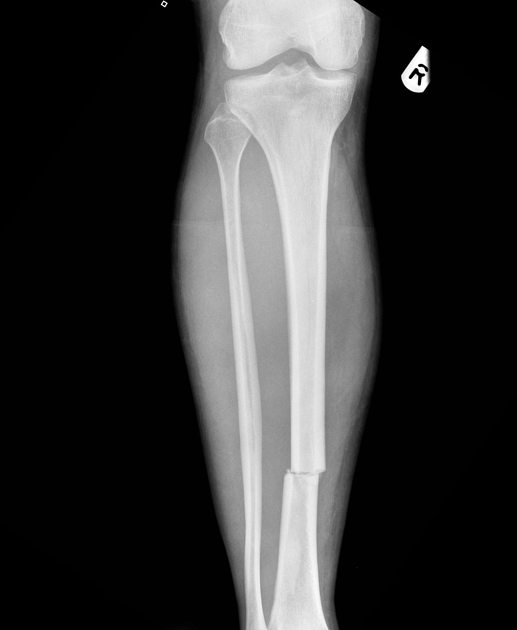

Transverse fracture - Definition

The fracture occurs at an exact 90° horizontal angle

Transverse fracture